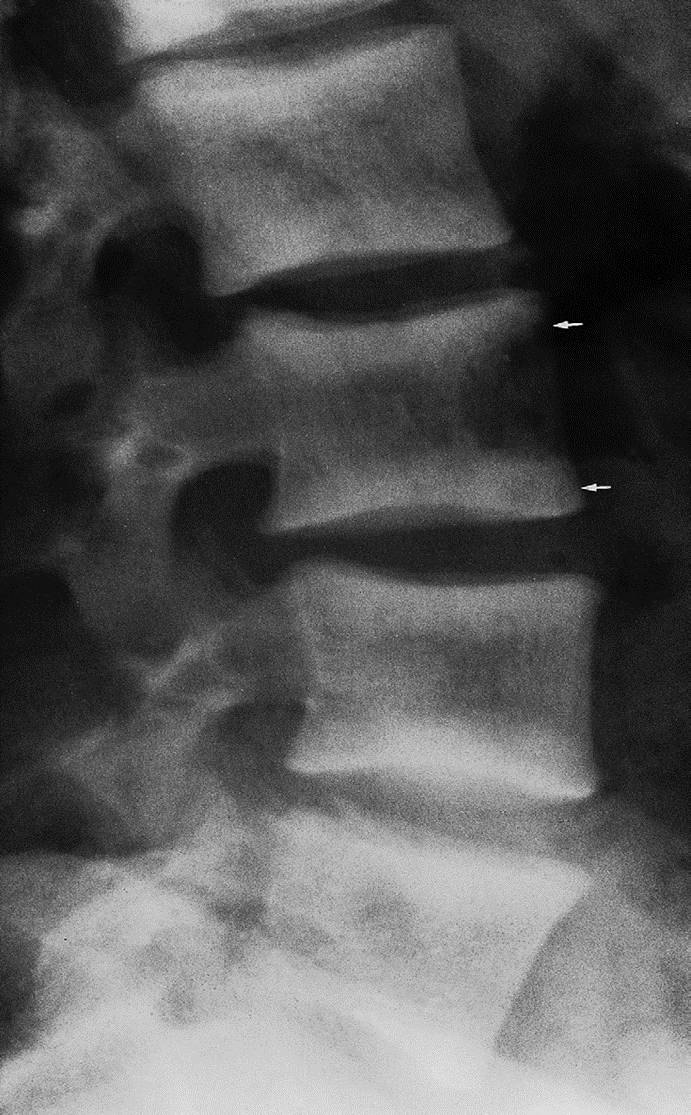

Ruger Jersey spine : secondary hyperparathyroidism z

Occurs due to renal failure/renal osteodystrophy prominent endplate densities at multiple contiguous vertebral levels to produce an alternating sclerotic-lucent-sclerotic appearance

On x-ray white margins with lucent central and vertical trabeculae, which is called( Ruger Jersey spine) these, (changes are due to renal dystrophy.

- Decreased bone density of the central portions (black area)

- Sclerotic vertebral end plates

(renal osteodystrophy). There are sclerotic bands running across the upper and lower ends of the vertebral bodies of the lumbar spine (arrows).